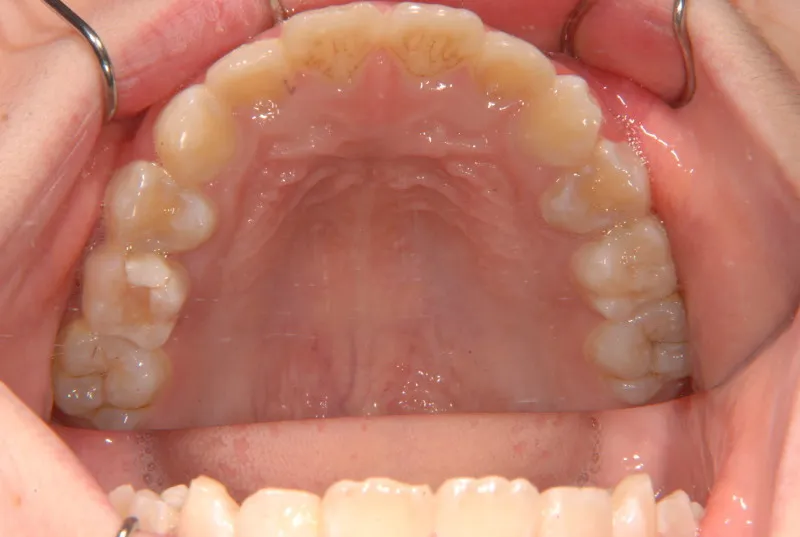

【子供の矯正(一期)】叢生・反対咬合・受け口・非抜歯症例・7歳女児【M.H様】

治療終了後

治療回数21回、2年7ヶ月の治療期間で矯正治療を終了しました。

主訴が改善され、ご満足頂きました。